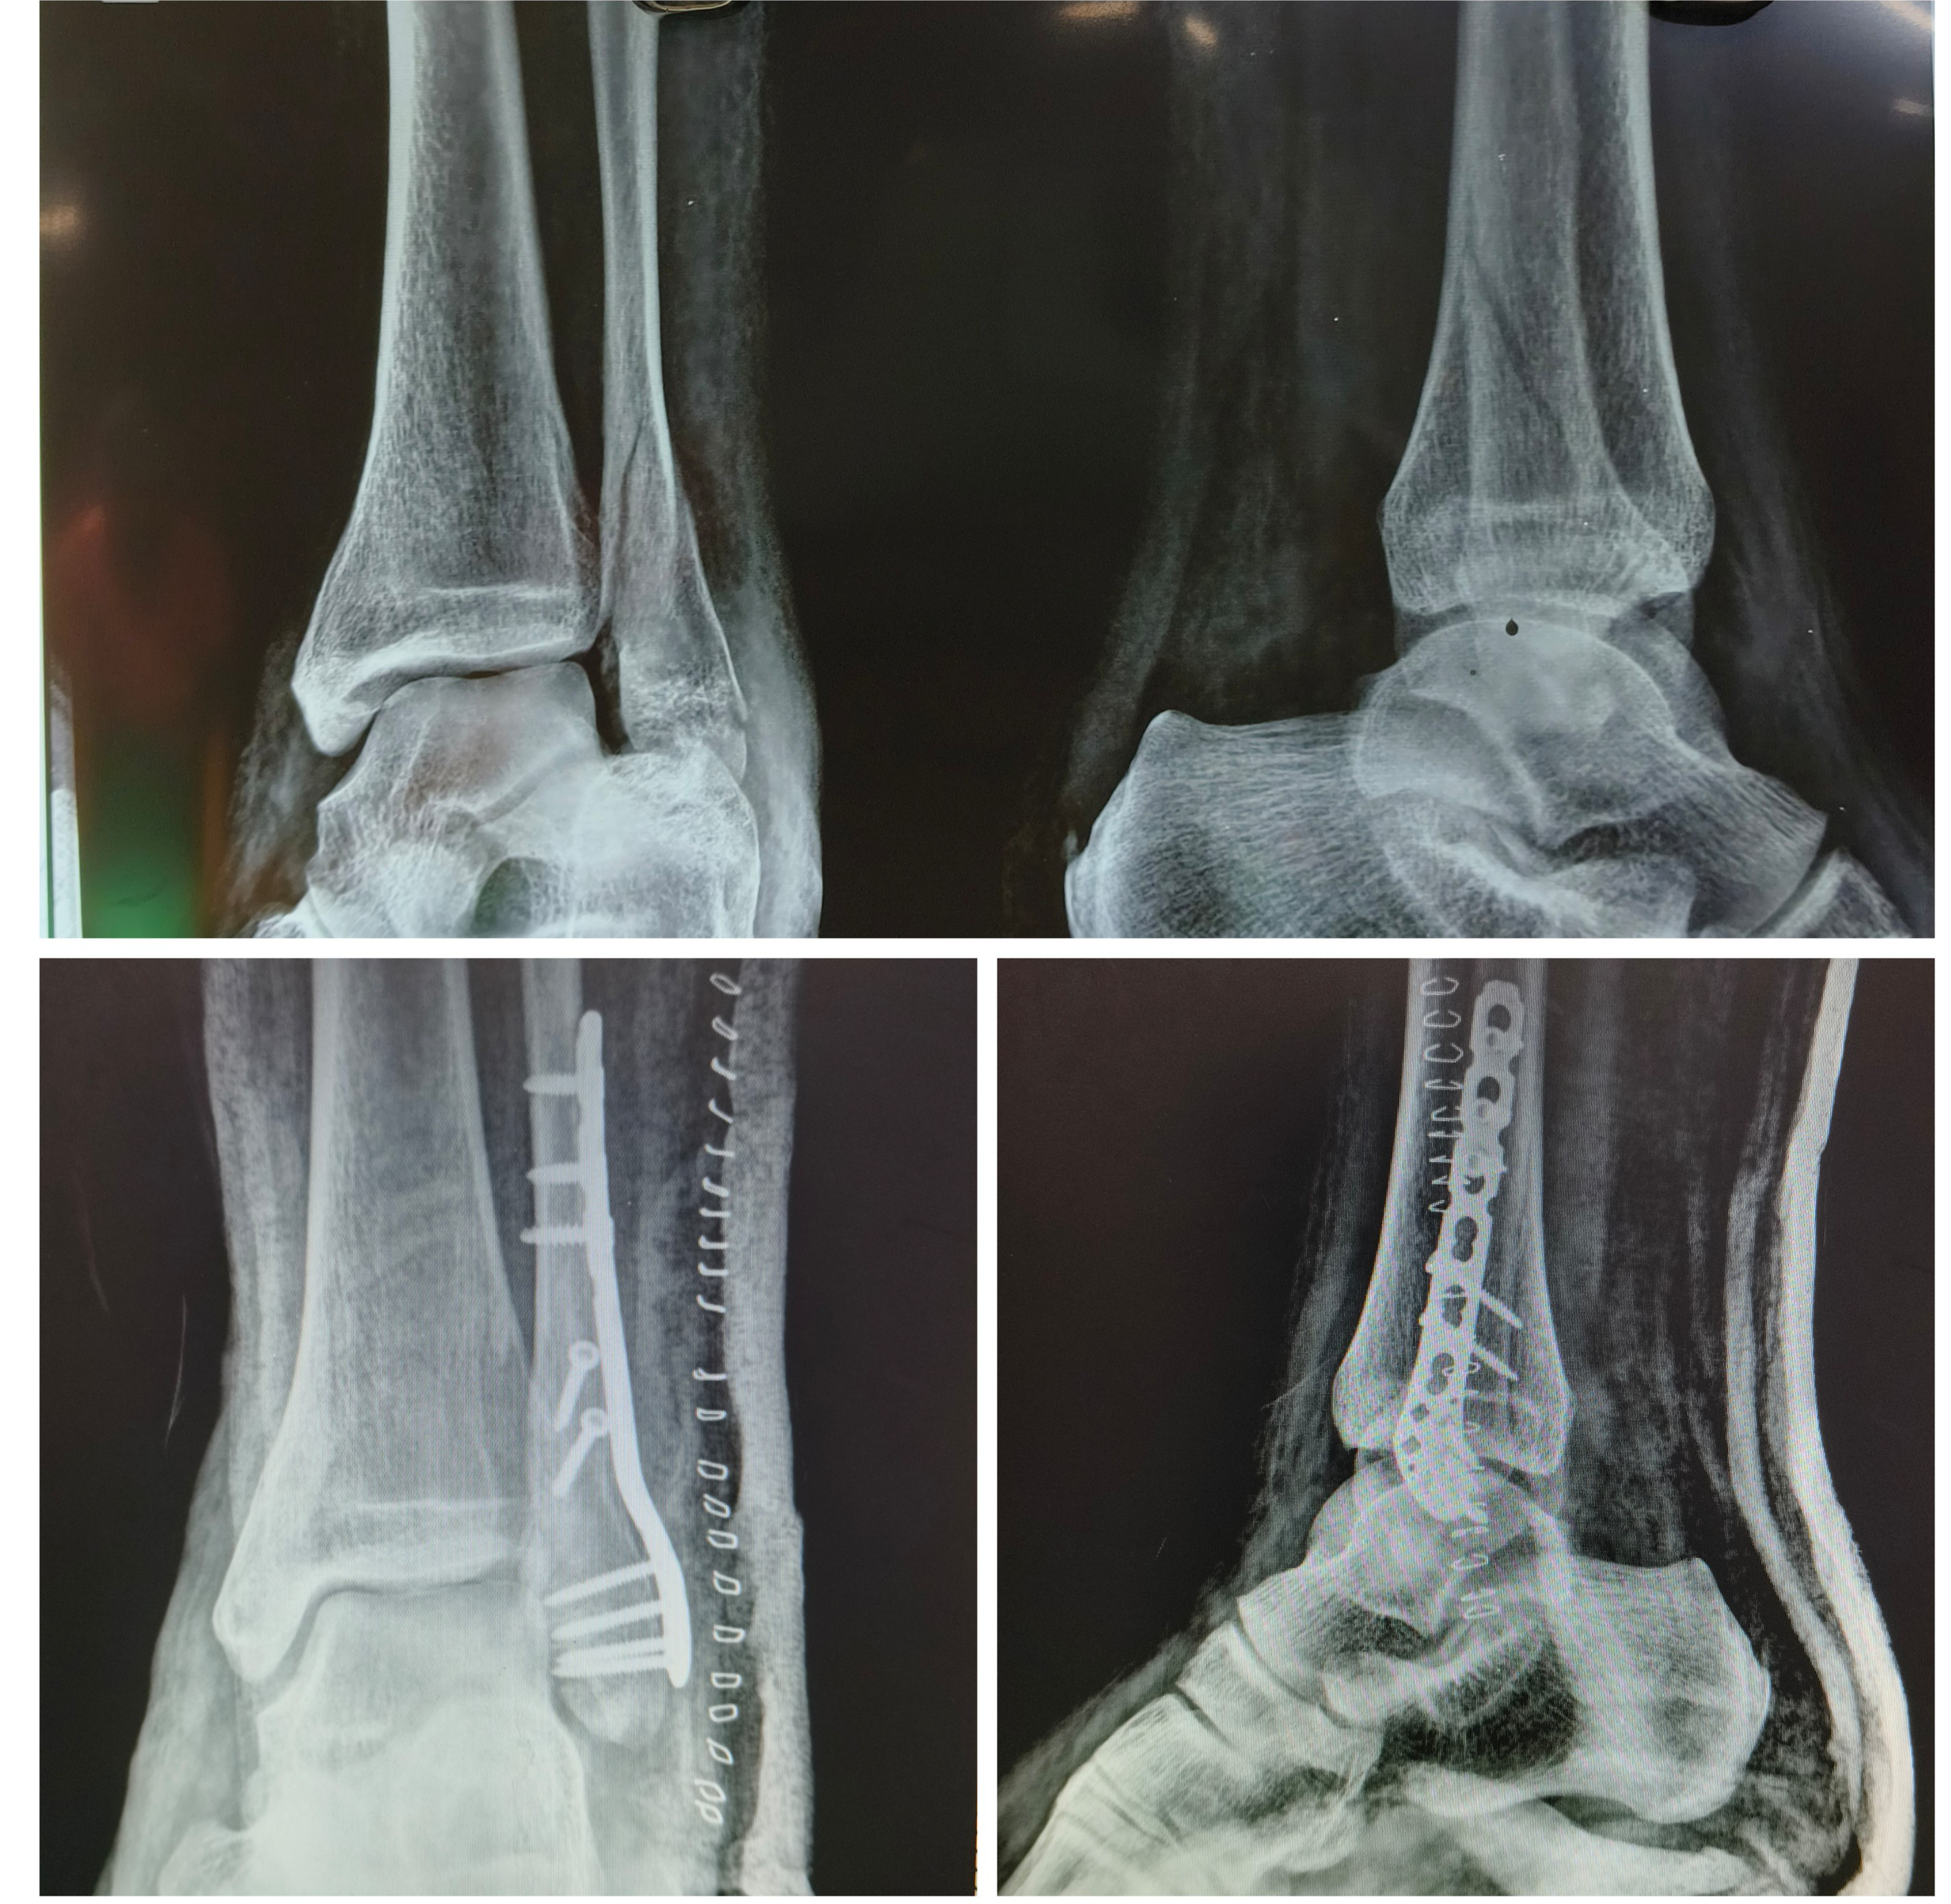

Young male had a fall while working, sustained injury to ankle. X-Ray shows lateral malleoli fracture. Patient was operated with open reduction and internal fixation with an anatomical fibula locking plate.